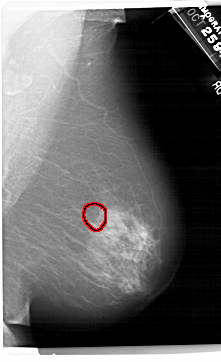

A_1495_1.RIGHT_CC

RIGHT_CC LINES 6871 PIXELS_PER_LINE 4021 BITS_PER_PIXEL 12 RESOLUTION 43.5 OVERLAY

FILE: A_1495_1.RIGHT_CC.OVERLAY

TOTAL_ABNORMALITIES 1

ABNORMALITY 1

LESION_TYPE CALCIFICATION TYPE AMORPHOUS DISTRIBUTION CLUSTERED

ASSESSMENT 4

SUBTLETY 4

PATHOLOGY BENIGN

TOTAL_OUTLINES 1

BOUNDARY